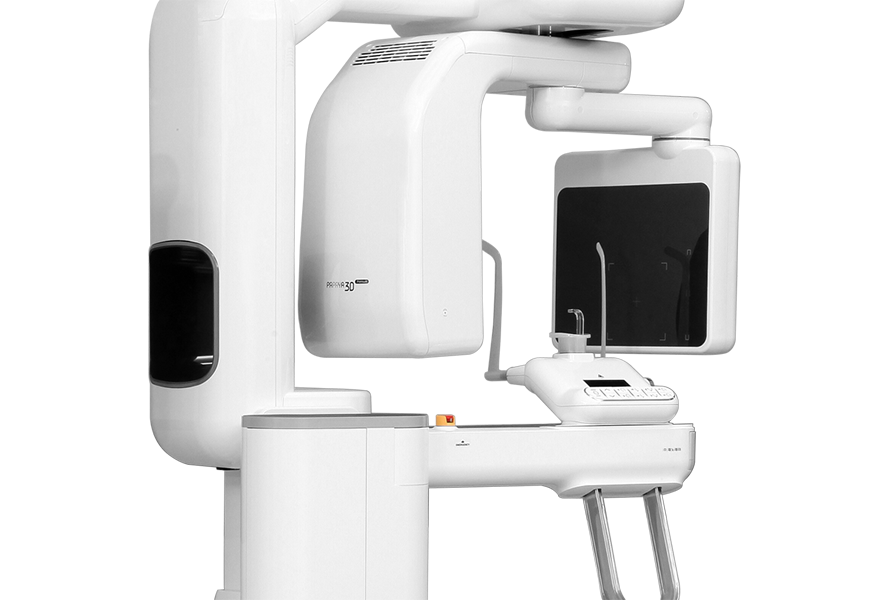

Превосходное качество изображения

Удобный доступ

Обновленная и функциональная система позиционирования пациента для любых вариантов расположения аппарата.Обеспечивает удобство для всех пациентов и экономит ваше пространство.